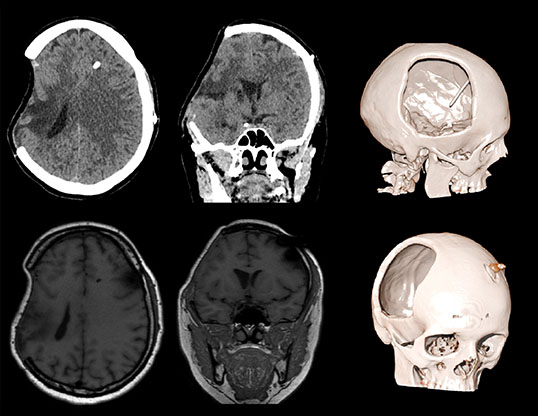

Пациент А., перенесший тяжелую черепно-мозговую травму в ДТП. Состояние после правосторонней гемикраниотомии, эвакуации крупной субдуральной гематомы. Произведена ликворошунтирующая операция с установкой программируемого клапана давления . Через месяц пациент стал предъявлять прогрессирующие неврологические расстройства.

Визуализируется обширная инвагинация кожного лоскута в полость дефекта, смещение срединных структур влево, сдавление САП правого полушария и сглаженность борозд. Причиной данного состояния явилась гиперфункция шунта.

Данному пациенту была произведена краниопластика дефекта черепа, коррекция программируемого клапана давления. Пациент выписан на третьи сутки в удовлетворительном состоянии с полным регрессом неврологической симптоматики.